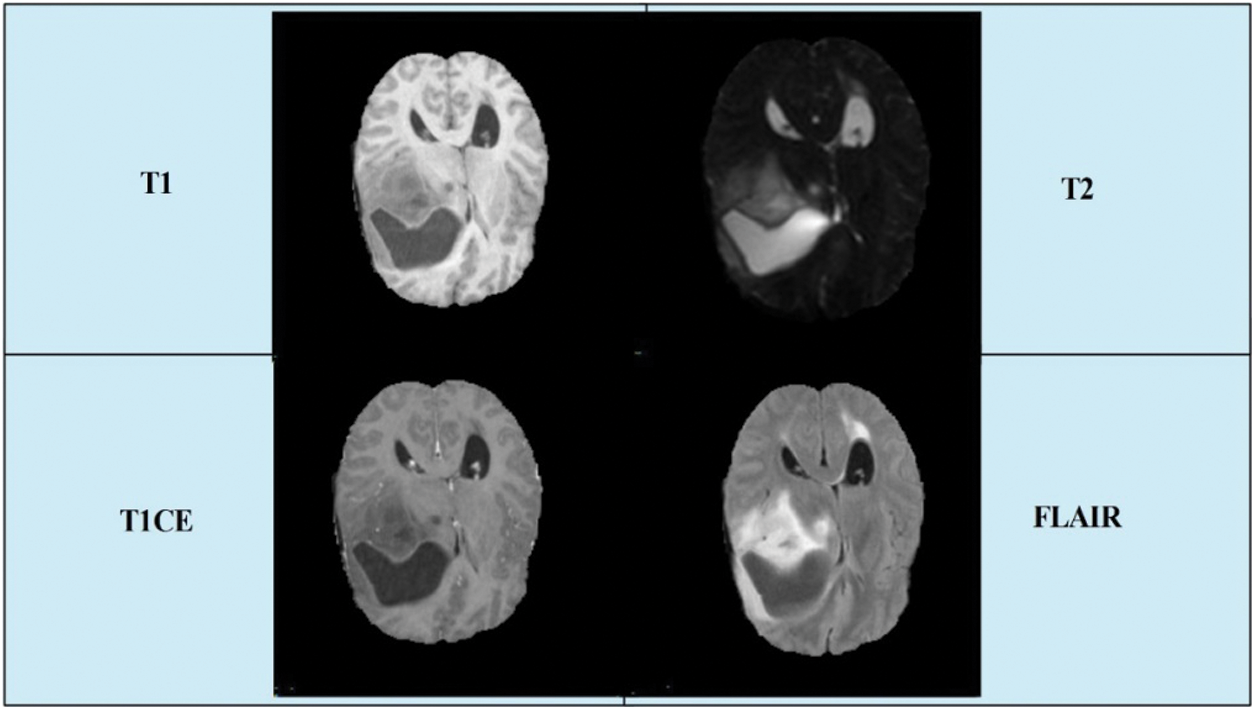

Today, an expected 700,000 individuals in the US live with an essential brain tumor, and roughly 85,000 more determinations are examined in 2021. In 2020, there are an estimated 78,980 cases diagnosed (https://braintumor.org/brain-tumor-information/brain-tumor-facts/). Early diagnosis of a brain tumor is essential for controlling the patient’s mortality rate. However, it is a complicated task owing to tumor size, shape, location, and type [4]. Radiologists used computerized tomography (CT), which is better than X-ray technology [5]. However, magnetic resonance imaging (MRI) is a new technology that is more useful than CT for the diagnosis of brain tumors [6]. Through this imaging technology, images of the patient’s body structures were produced. For each patient, four types of MRI scans were generated: T1 weighted, T1 contrast enhanced, T2 weighted, and Flair [7]. A few sample images are presented in Fig. 1.

Figure 1: A few sample images collected from BRATS2019 dataset

In this study, we utilized the BraTs 2019 brain dataset that includes both high-grade glioma (HGG) and low-grade glioma (LGG). The images in this dataset are in MRI format, and each for each patient, four types of scans were generated: T1, T1CE, T2, and Flair. A few sample images are shown in Fig. 1. This dataset consisted of 259 cases of HGG and 76 cases of LGG. All images were manually annotated by clinicians and certified radiologists [24]. In the normalization step, we normalize this dataset into four folders, which are further divided into training and testing. The details of this normalized dataset are listed in Tab. 1.